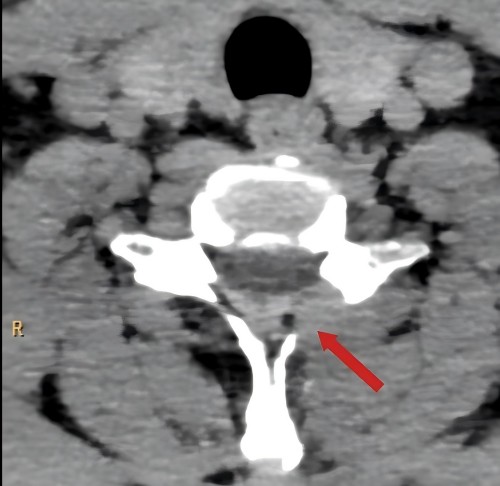

术前检查提示:C6/7椎间盘突出,左侧神经根受压

术后复查CT显示:减压彻底